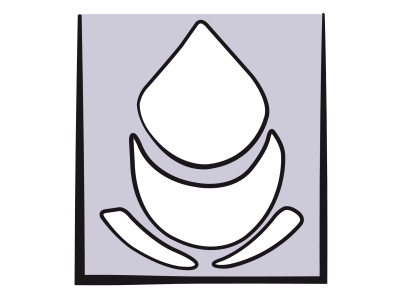

Il n'existe aucune mesure directe de la volémie utilisable en clinique. On se réfère habituellement à la détermination de valeurs de substitution, telles la pression artérielle ou la pression veineuse centrale (PVC). Or la pression et le volume de remplissage sont reliés entre eux par la compliance de la cavité cardiaque. Cette relation est curvilinéaire : les variations de pression (ΔP) sont minimes par rapport aux variations de volume (ΔV) à bas volume de remplissage parce que la courbe de compliance est quasi-horizontale en hypovolémie, mais importantes à haut volume parce que la courbe se redresse (Figure 27.1) [10]. De ce fait, la corrélation de la PVC à la volémie est inexistante lorsque la précharge est basse (r = 0.3-0.5) [22].

Figure 27.1 : Courbe de compliance du ventricule. La courbe normale (en bleu) est curvilinéaire. En hypervolémie, une variation du volume de remplissage (ΔV) se traduit par une variation significative de la pression télédiastolique (PVC ou PAPO) parce que la courbe est bien redressée. En hypovolémie, au contraire, la courbe est très plate, et une variation de volume (ΔV') même importante ne provoque qu'une modification minime, voir non mesurable, de la pression de remplissage (ΔP'). Ce phénomène invalide la mesure de la PVC ou de la PAPO comme indice d'hypovolémie. En cas de dysfonction diastolique, la courbe de compliance (en rouge) est déplacée vers le haut (la pression de remplissage est plus élevée pour le même volume) et redressée dès son origine.

Il n'existe aucune mesure directe de la volémie utilisable en clinique. On se réfère habituellement à la détermination de valeurs de substitution, telles la pression artérielle ou la pression veineuse centrale (PVC). Or la pression et le volume de remplissage sont reliés entre eux par la compliance de la cavité cardiaque. Cette relation est curvilinéaire : les variations de pression (ΔP) sont minimes par rapport aux variations de volume (ΔV) à bas volume de remplissage parce que la courbe de compliance est quasi-horizontale en hypovolémie, mais importantes à haut volume parce que la courbe se redresse (Figure 27.1) [10]. De ce fait, la corrélation de la PVC à la volémie est inexistante lorsque la précharge est basse (r = 0.3-0.5) [22].

Figure 27.1 : Courbe de compliance du ventricule. La courbe normale (en bleu) est curvilinéaire. En hypervolémie, une variation du volume de remplissage (ΔV) se traduit par une variation significative de la pression télédiastolique (PVC ou PAPO) parce que la courbe est bien redressée. En hypovolémie, au contraire, la courbe est très plate, et une variation de volume (ΔV') même importante ne provoque qu'une modification minime, voir non mesurable, de la pression de remplissage (ΔP'). Ce phénomène invalide la mesure de la PVC ou de la PAPO comme indice d'hypovolémie. En cas de dysfonction diastolique, la courbe de compliance (en rouge) est déplacée vers le haut (la pression de remplissage est plus élevée pour le même volume) et redressée dès son origine.